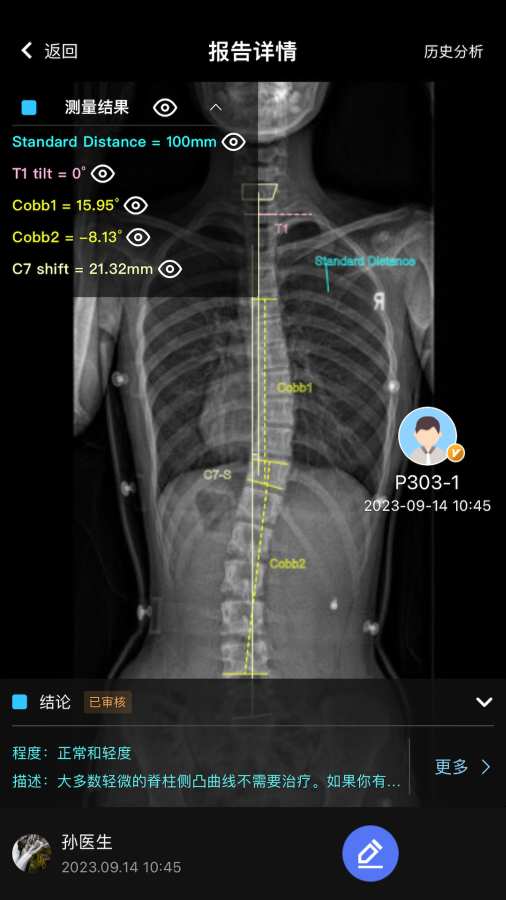

2.AI智能化分析病情,医生可编辑审核诊疗报告;

5.上传病人影像,支持x光等;